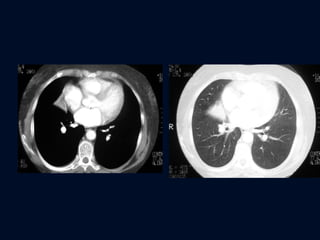

ATELECTASIA LÓBULOS INFERIORES Bronquio lobar desplazado posterior y medialmente Arteria pulmonar no es visible no hay interfase  Lateral: sombra triangular posterior al surco costofrénico Porción anterior es cóncava

ATELECTASIA LÓBULOS INFERIORES La mayor densidad representa pulmón colapsado debajo de un lóbulo medio y superior expandidos Caso extremo  Franja en posición paravertebral

ATELECTASIA LÓBULO INFERIOR DERECHO